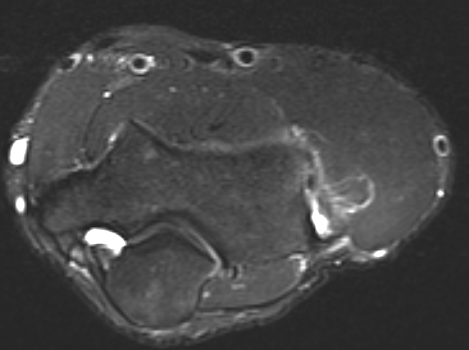

MRI

High grade partial tears of ECRB on lateral eipcondyle

Tendonopathy of the common extensor origin, with thickening and high grade tear partial tear